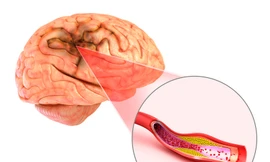

Long Châu phối hợp Bộ Y tế triển khai chương trình quốc gia về phòng và quản lý đột quỵ

Ngày 29/10/2025, nhân ngày Thế giới phòng chống Đột quỵ, hệ thống nhà thuốc và trung tâm tiêm chủng Long Châu đồng hành cùng Bộ Y tế, Hội Thầy thuốc trẻ Việt Nam, Công ty TNHH Bayer Việt Nam chính thức khởi động chương trình “Hợp tác chiến lược Quốc gia về phòng và quản lý đột quỵ tại Việt Nam”.